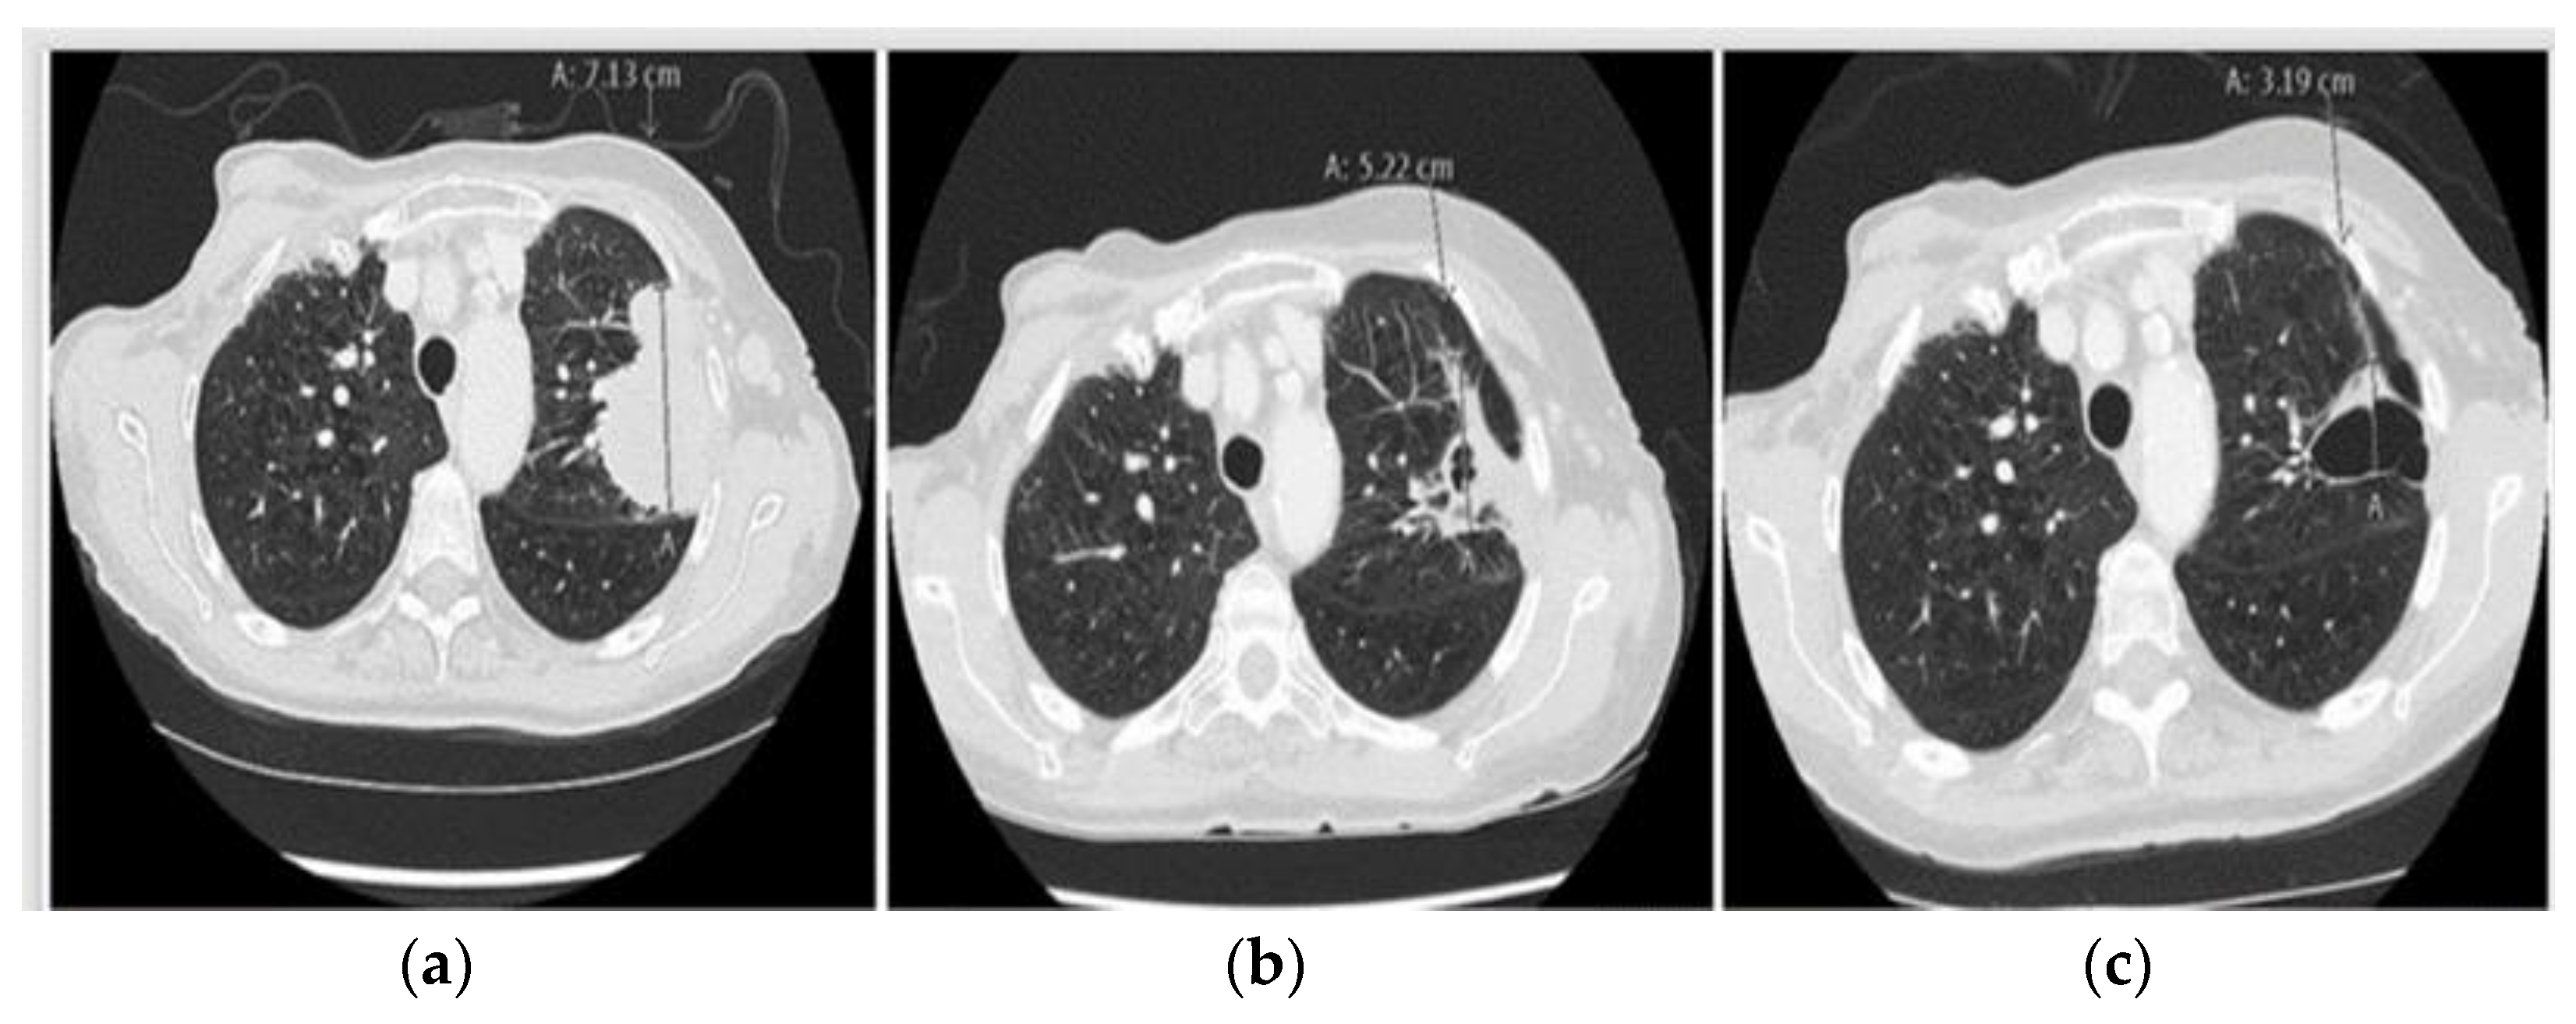

2.1. Case 1: Metastatic NSCLC with EGFR ex19del and Acquired MET Amplification: Short-Term Complete Response (CR) by Combining Crizotinib with Osimertinib

2.5. Case 5: Efficacy of Crizotinib-Osimertinib in EGFRm+ NSCLC Patient Acquiring High-Level MET Amplification after 26 Months of Treatment with Osimertinib